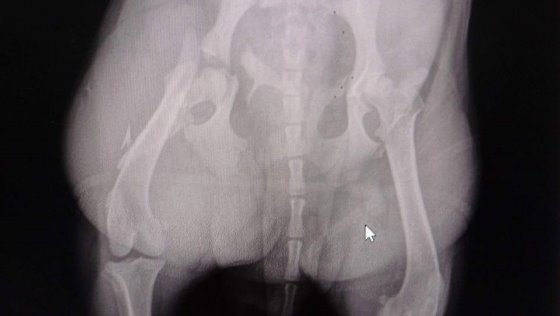

Życie Gammy jest w niebezpieczeństwie Emotikon frown Emotikon frown Emotikon frown Dziś sunia zaczęła się pokładać. Szybko podjęto badania. Okazało się, że ma przepuklinę przeponową, spowodowaną uderzeniem przez samochód. Jelita przez rozerwaną przeponę przemieściły się do klatki piersiowej Emotikon frown Dziś w nocy sunia przejdzie poważną operację. Trzymajcie kciuki.